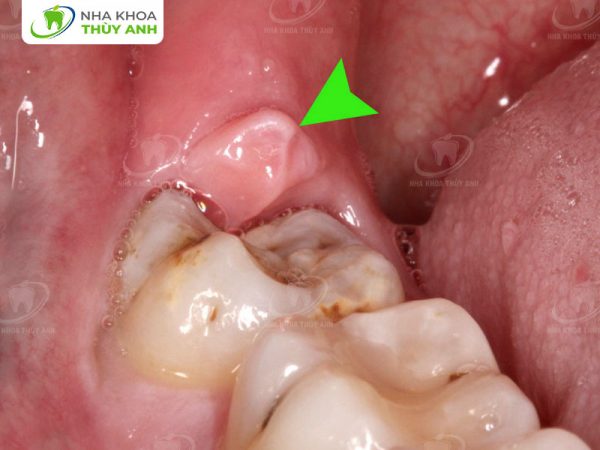

- Răng mọc lệch, đâm vào răng số 7 bên cạnh.

- Răng mọc ngầm trong nướu, không thể trồi lên hoàn toàn.

- Răng mọc thẳng nhưng không đủ chỗ, gây đau nhức và sưng nướu.

- Răng mọc lệch hoặc ngầm: Đây là tình trạng phổ biến nhất, gây áp lực lên răng số 7 hoặc các mô xung quanh, dẫn đến đau nhức, viêm nhiễm.

- Răng khôn gây tổn thương răng bên cạnh: Khi răng khôn đâm vào răng số 7, nó có thể gây sâu răng hoặc viêm nha chu, ảnh hưởng đến chức năng của răng này.